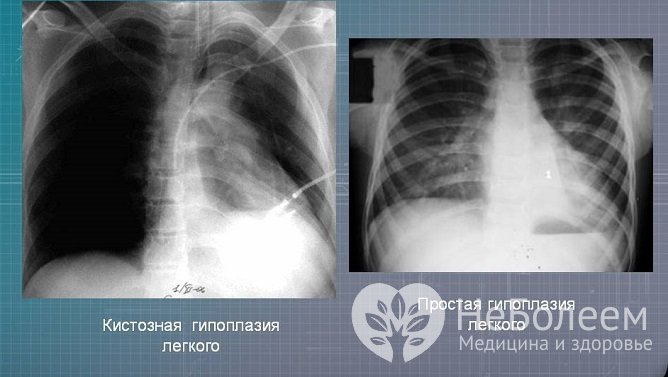

Клинические проявления гипоплазии легких определяются объемом поражения. Если патология затрагивает не более 1-2 сегментов, то она протекает бессимптомно. При более объемных поражениях у ребенка возникают следующие симптомы:

Гипоплазия легких сопровождается частыми воспалительными процессами.

Наиболее тяжелый прогноз отмечается при гипоплазии легких и головного мозга. Эти состояния приводят к инвалидизации пациентов, а нередко и к летальному исходу. Наиболее благоприятен прогноз при гипоплазии зубов.